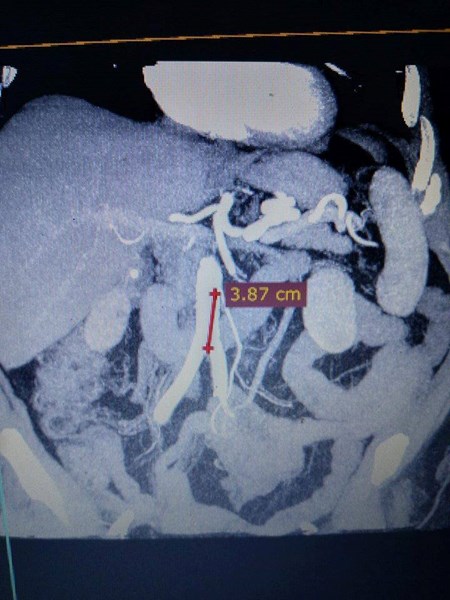

Иновативното е, че част от операцията е симулирана предоперативно на 3D медицинската маса за виртуални дисекции. На нея хирурзите са изучили анатомията на пациентката, дискутирали са най-подходящите входове за ръцете на роботизираната система в коремната кухина, за да се осигури оптимална позиция за балансирана работа на двата екипа. Подобен тип операции все още се извършват предимно чрез отворена хирургия, което води до голяма травма за пациента, поясниха от университета в Плевен.

Проф. Горчев коментира сложната операция така: "След клинично обсъждане на случая от екипите от хирурзи и гинеколози, взехме решение за извършване на тази изключително сложна операция с роботизираната система da Vinci Si, при която едновременно да се отстранят правото черво и матката на пациентката, т.н. задна тазова екзантерация. В същото време да се възстанови чревния тракт с ултраниска шевна линия на дебелото и правото черво."